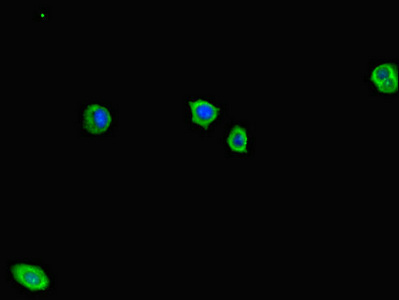

Immunofluorescent analysis of HepG2 cells using CSB-PA600142LA01HU at dilution of 1:100 and Alexa Fluor 488-congugated AffiniPure Goat Anti-Rabbit IgG(H+L)